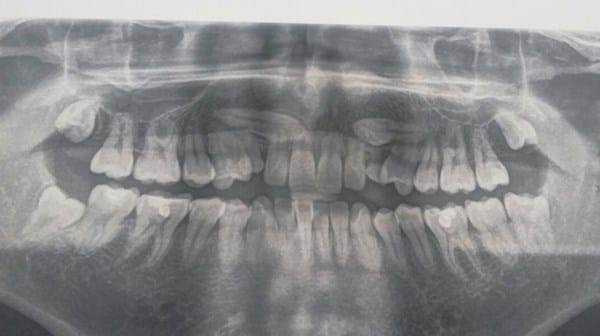

El ortodoncista me pidió que me realizara una radiografía panorámica, donde se dio cuenta que los caninos se hallan impactados en el hueso, y están en una posición totalmente horizontal (acostados), con el tiempo también se movieron de lugar, ya que prácticamente están ubicados arriba de los incisivos (entre los incisivos centrales y laterales, cada uno ) .

Debido a esta posición, el ortodoncista, temía que los colmillos impactados hubieran dañado las raíces de los incisivos, así que me pidió una tomografía maxilar 3D.

(Aquí mi radiografía)